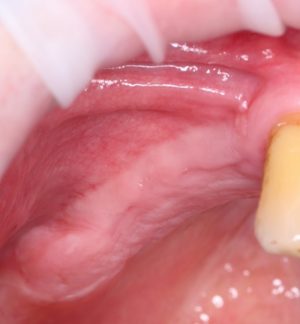

Например, он позволяет из этого:

сделать вот это с минимальными усилиями и травматичностью:

Другими словами, коллагеновая матрица Geistlich Mucograft позволяет увеличить зону прикрепленной кератинизированной десны в области имплантатов или естественных зубов без использования донорского участка и собственной слизистой оболочки, что существенно снижает травматичность и возможные риски осложнений, сопровождающих подобные хирургические вмешательства.